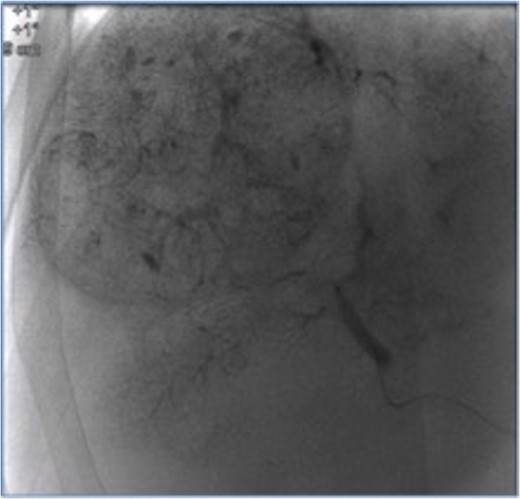

The S8 HCC lesion was successfully treated with TACE (lipiodol-epirubicin injection), while the second lesion was resected laparoscopically with a lateral left sectionectomy and a complete lymphadenectomy of the hepatic pedicle and coeliac trunk, including a large lymph node of the common hepatic artery (Figs 2 and 3).

Segment 8 nodule treated with transarterial chemoembolization.